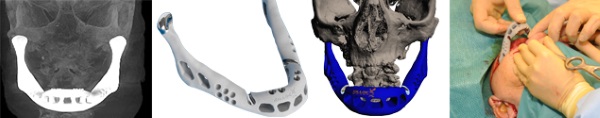

В 2012 году бельгийские и голландские ученые удачно заменили нижнюю челюсть 83-летней женщины на 3D-печатную модель. Титановый протез был напечатан компанией LayerWise. Операцию провели в июне в госпитале Sittard-Geleen, а на следующий день женщина уже могла разговаривать.